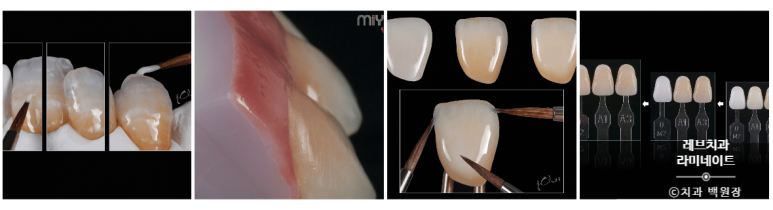

치료하기 전 치아의 색상을 채득해 두어야 합니다.

VITA shade guide를 사용하여, 치아를 깎아내기 전에 색상을 미리 기록해둡니다.

레브네이트 엑스퍼트를 완성하는데 3일의 시간이 소요되었습니다.

레브네이트 엑스퍼트의 경우 자연스러운 아름다움을 만들어드리기 위해, 보이는 라미네이트 면 위에 색상을 입체적으로 표현하는 세라믹 재질을 얹기도 하고 도료로 컬러링을 하기도 합니다.

그래서 원데이는 조금 어렵고, 예약 후 치료하실 경우 3일 정도 시간의 여유를 주셔야 한답니다. (그래도 빠른거에요!!!!)

정말 정말 왠만한 치과에서는 구사하지 못하는 디테일이라고 할 수 있습니다.

모든 라미네이트를 자체 제작하는 치과는 정말 정말 드물거든요... 그만큼 수작업이 많이 들어가는 라미네이트입니다. 하나하나가 '전담 세라미스트'의 예술 작품이지요.